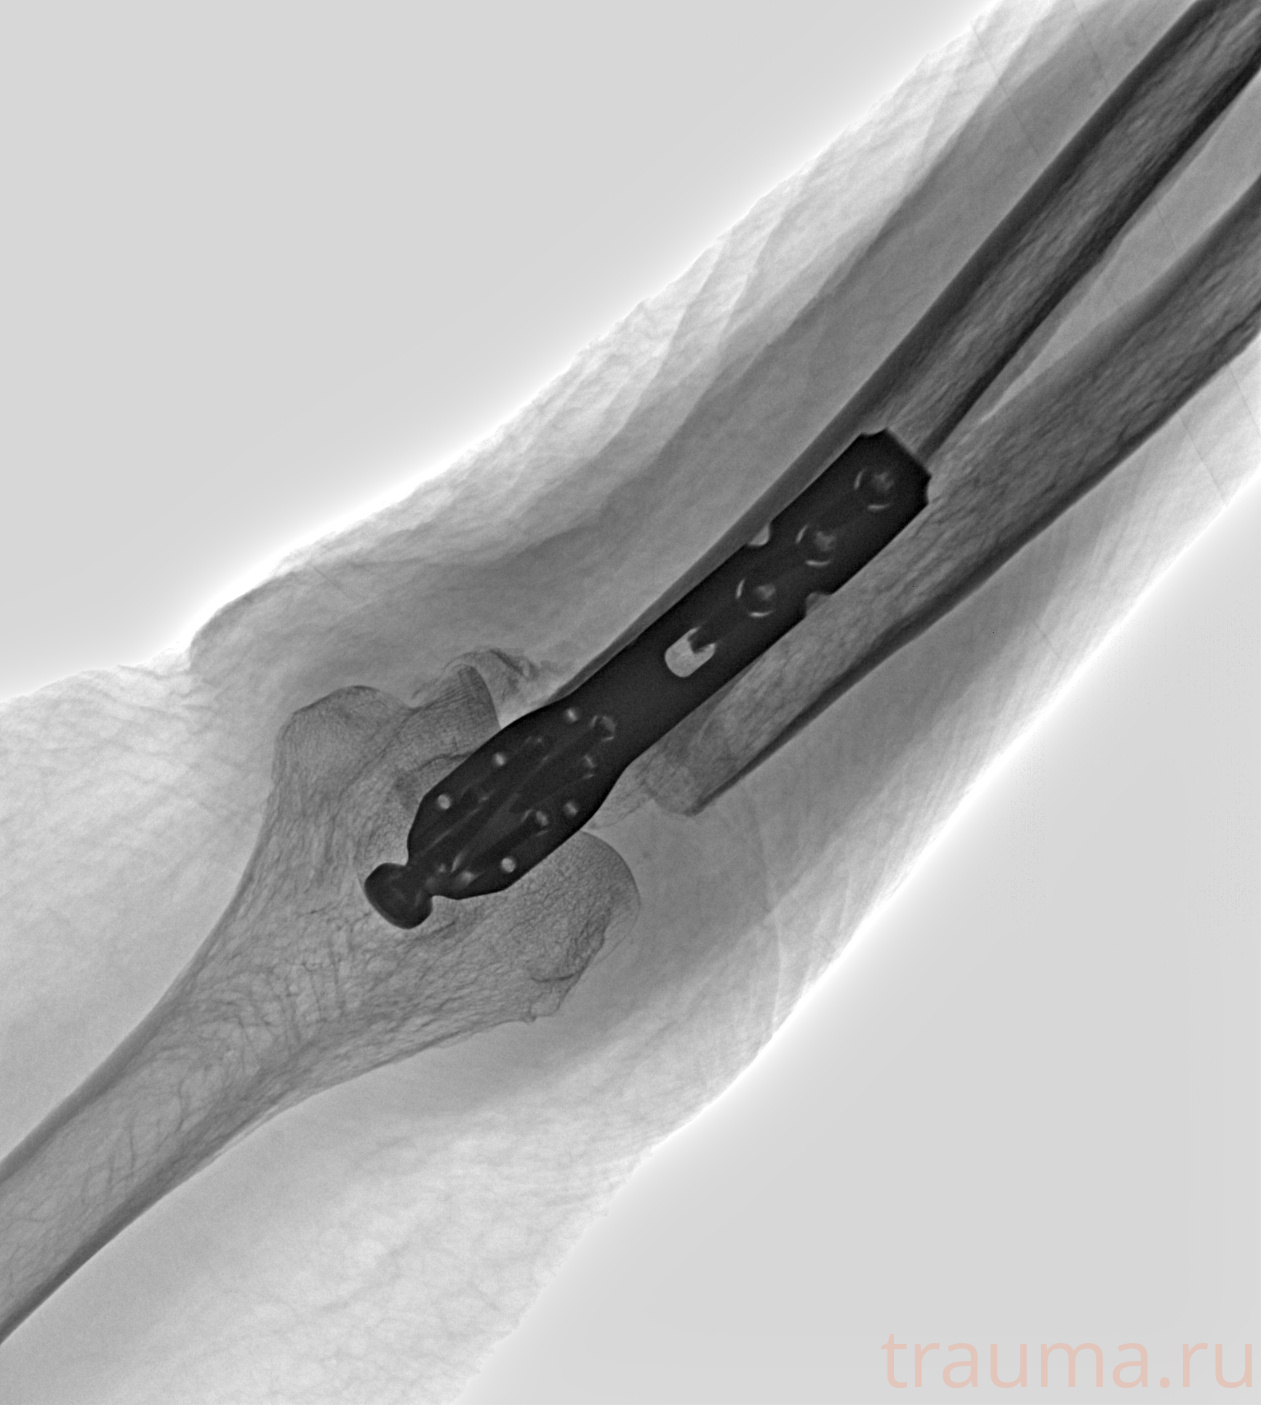

Рентгенограммы